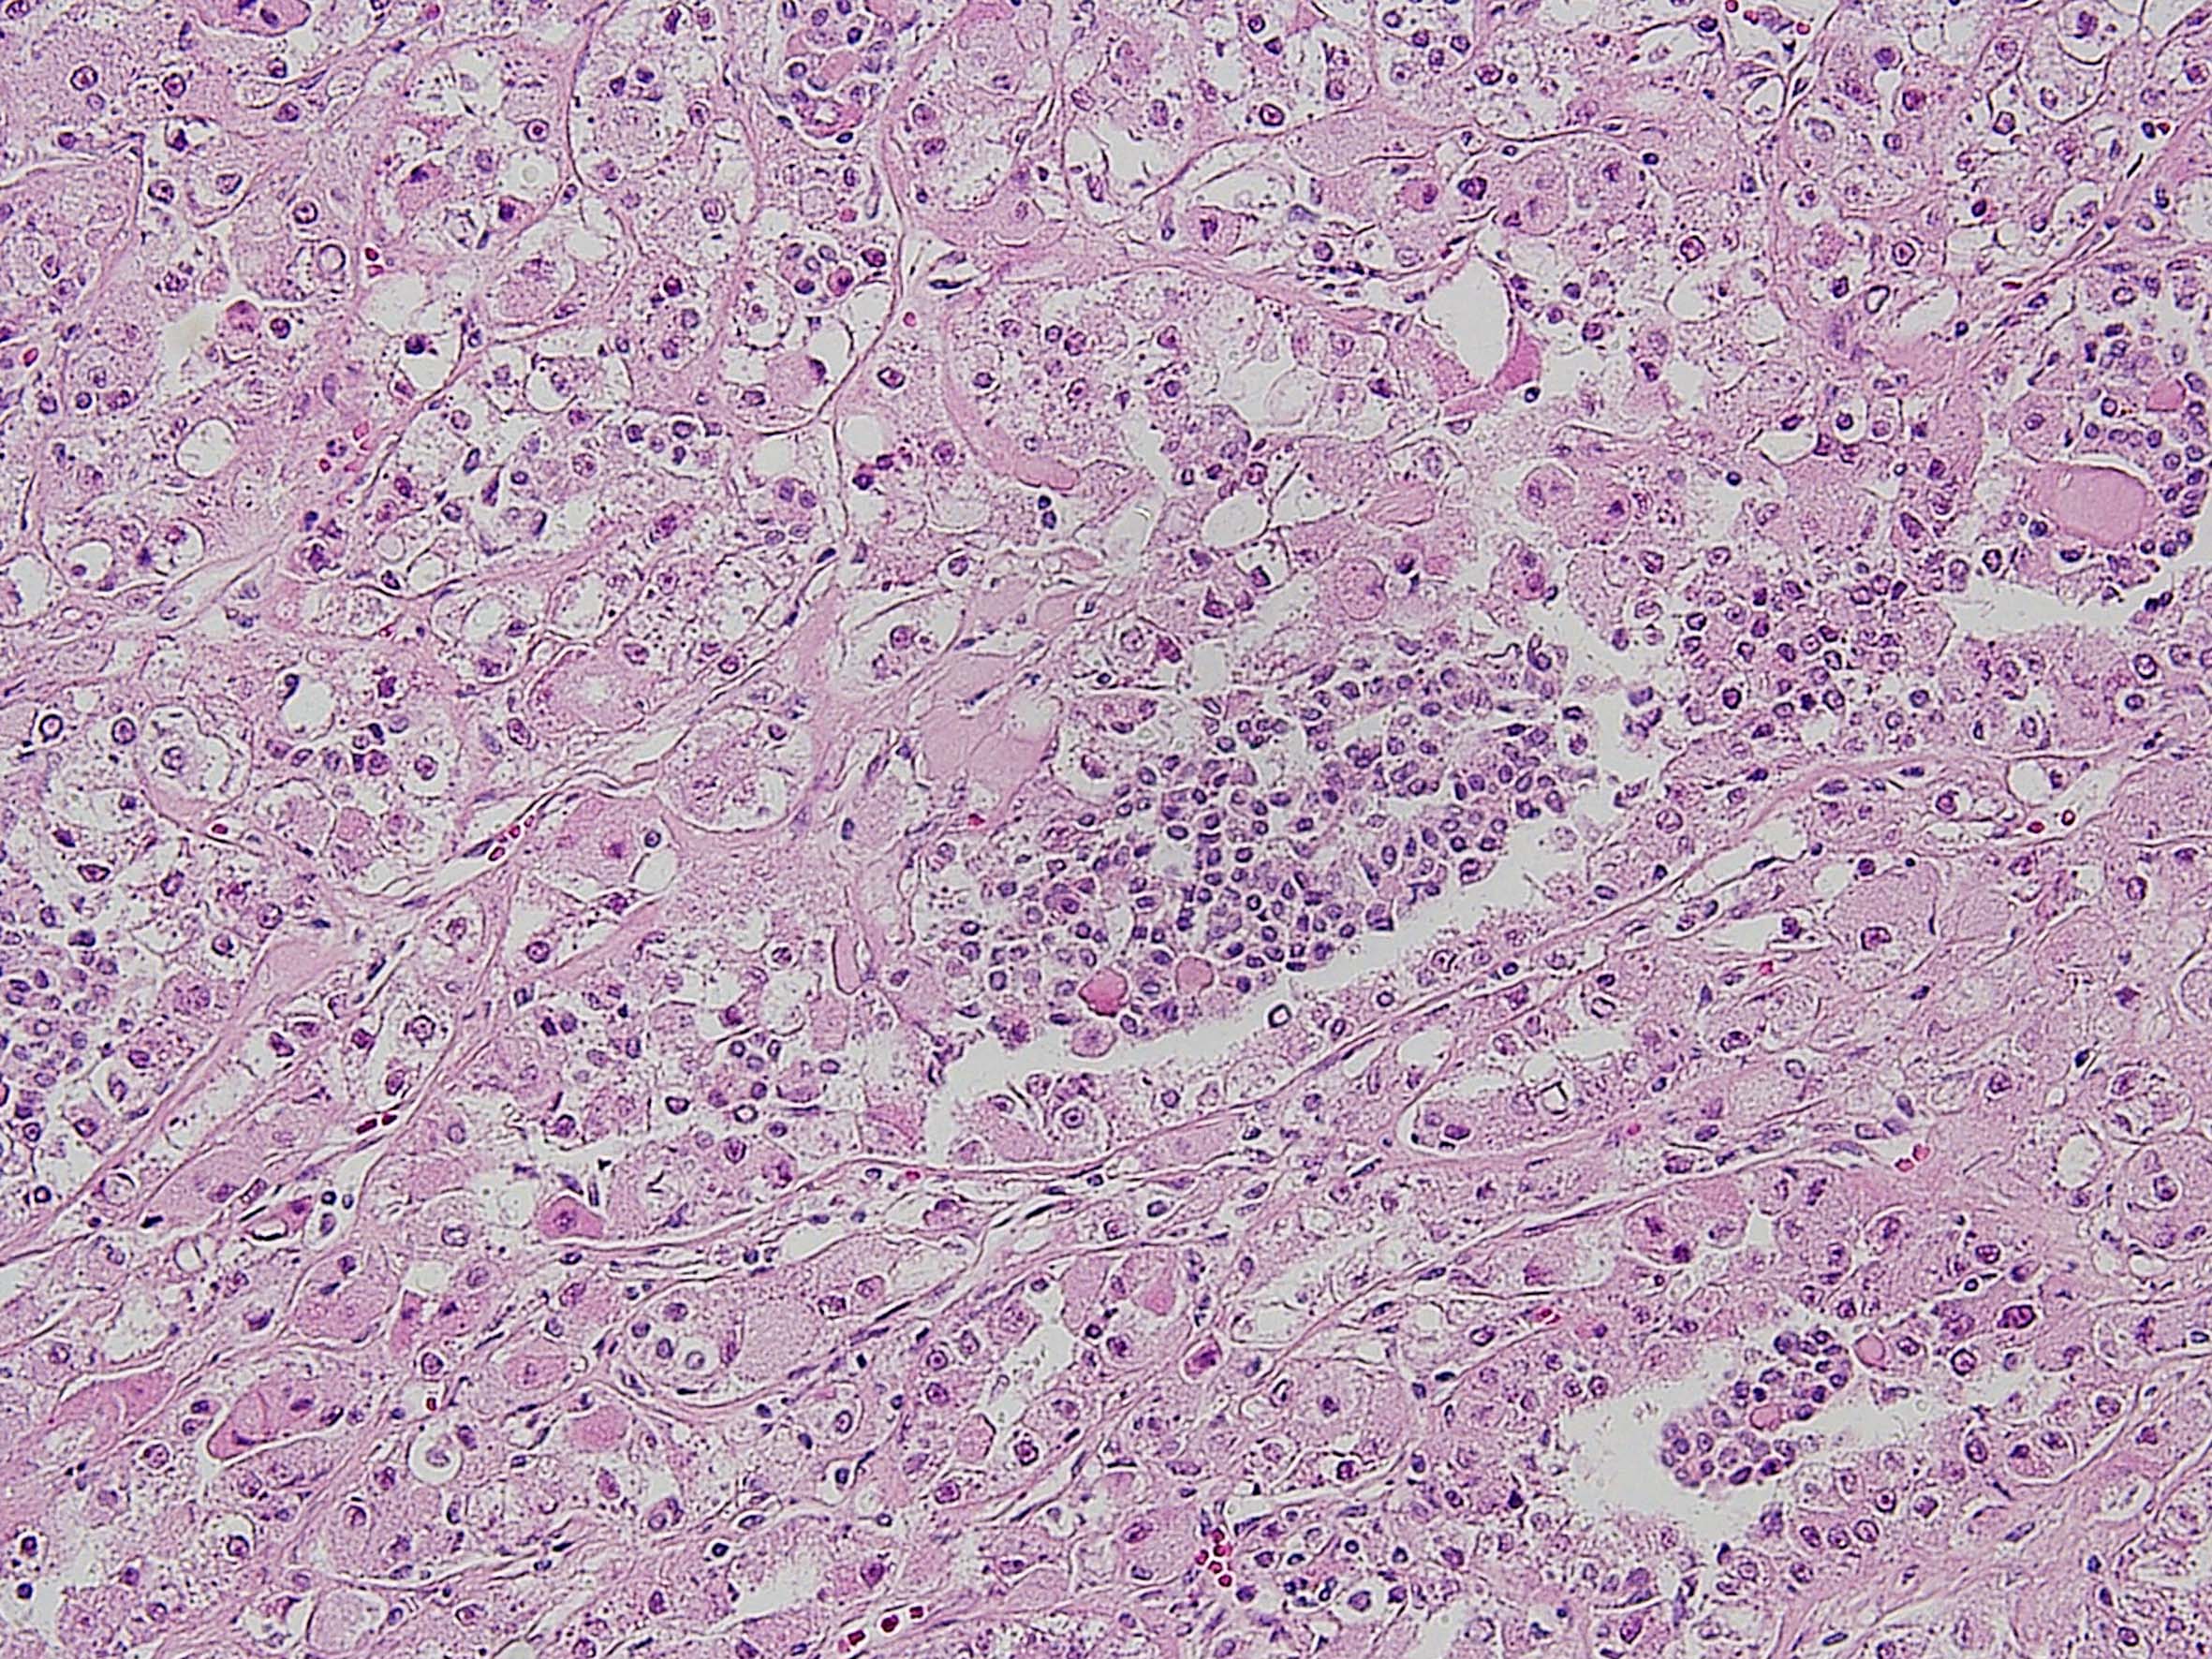

Consensus grade: MiT Family translocation carcinoma

MiT family translocation renal cell carcinoma. t(6;11) translocation

Section courtesy of Dr P Argani